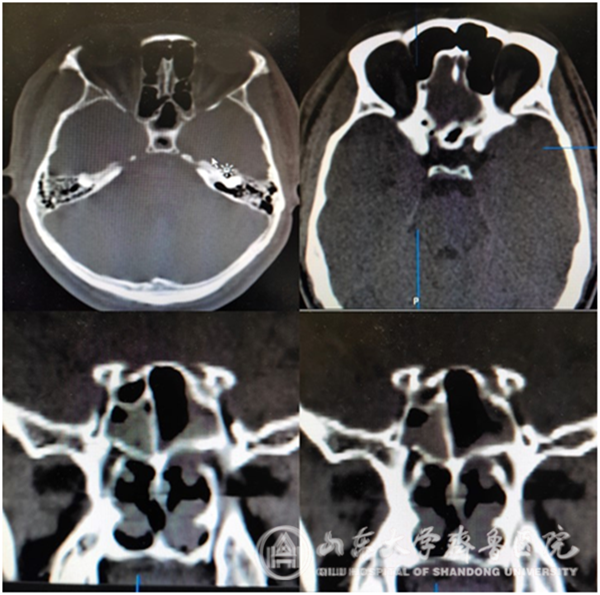

(术前可见视神经管及眶内侧壁骨折)

患者青年男性,18小时前骑电动车摔倒,并意识丧失,恢复意识后感右眼视力下降,自诉无光感,急症由外院转入我科。术前患者右眼无光感,对光反射消失,瞳孔直径5cm,左眼正常。主任医师徐淑军决定采取内镜下视神经减压术,手术由副主任医师李超进行,并在功能内镜组成员主治医师杨宁协助下完成。手术过程如下,患者全麻下取仰卧位,消毒并收敛双侧鼻腔粘膜,置入0度神经内镜,切断右侧中鼻甲,高速磨钻磨除右侧钩突及筛泡,咬除粘膜,显露右侧眶内侧壁、眶尖及视神经管。可见眶内侧壁骨折及陈旧性血肿,予以清除。磨钻及椎板咬骨钳去除眶内侧壁、眶尖及右侧视神经管下壁骨质,充分显露右侧视神经鞘,使用尖刀自眶尖至视神经人颅处切开视神经鞘,可见视神经肿胀明显,并有部分破碎的视神经流出,减压充分后,使用鼻中隔粘膜瓣修补脑脊液漏口,手术顺利结束。术后给予营养神经治疗,术后第6天患者自述右眼开始有光感,手术效果满意,出院继续营养神经支持治疗。